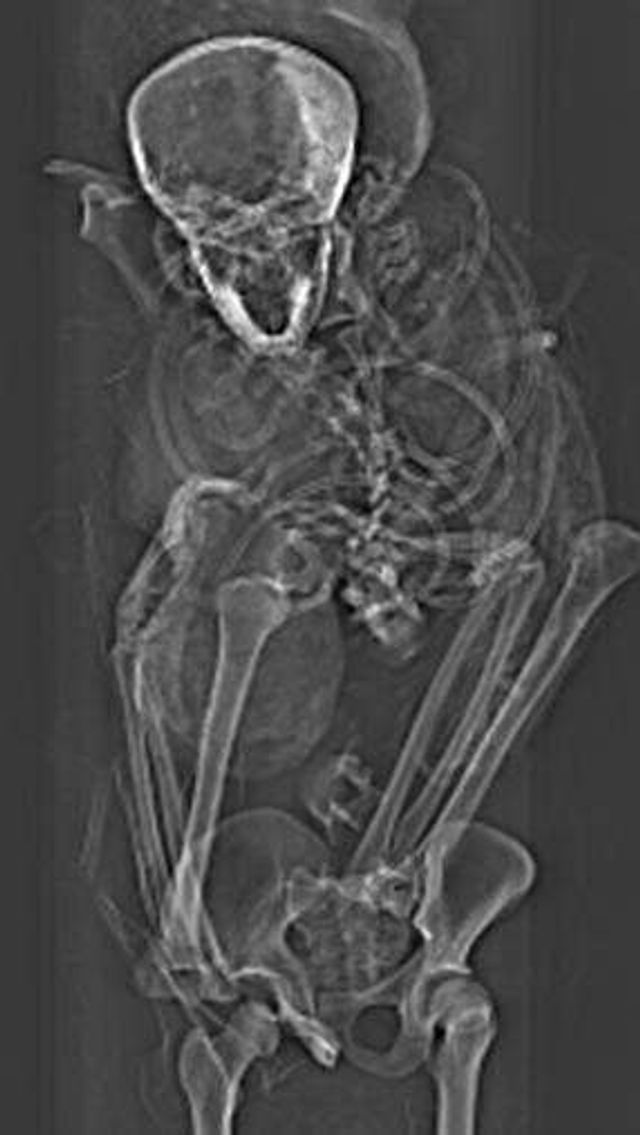

Комп'ютерна томографія єгипетської мумії дозволила встановити причину смерті фараона Секененра Таа II, що правив приблизно в 1569-1554 роках до нашої ери.

Сучасні медичні технології допомогли вченим дізнатися подробиці останніх годин життя фараона Секененра Таа II. Вважається, що цей фараон почав боротьбу з гіксосами – народом, який завоював частину Стародавнього Єгипту в XVIII-XVI століттях до нашої ери. З їх вторгненням почався період політичного розколу в Єгипті, який тривав з 1650 по 1549 рік до нашої ери.

Причину смерті фараона вчені намагаються з'ясувати з того часу, як виявили його мумію в Дейр-ель-Бахрі в 1881 році. Згідно з основною гіпотезою, Секененра Таа II потрапив в полон під час бою, а потім був страчений, можливо, ватажком гіксосів. Існує також інша версія, згідно з якою фараон був убитий уві сні в результаті палацової змови.

Поганий стан мумії наводив на думку, що бальзамування проводилося в поспіху, далеко від королівської майстерні муміфікації. Попередні дослідження дозволили виявити сліди травм на черепі. Вчені вважають, що насильницька смерть Секененра спонукала його наступників продовжити боротьбу за об'єднання Єгипту.

Нове дослідження, проведене за допомогою комп'ютерного томографа, дозволило виявити раніше непомічені пошкодження, які бальзамувальникам вдалося майстерно приховати. Це доводить, що муміфікація проводилася в добре обладнаному місці справжніми професіоналами своєї справи. Характер травм підтверджує раніше висунуту версію про полонення в бою.